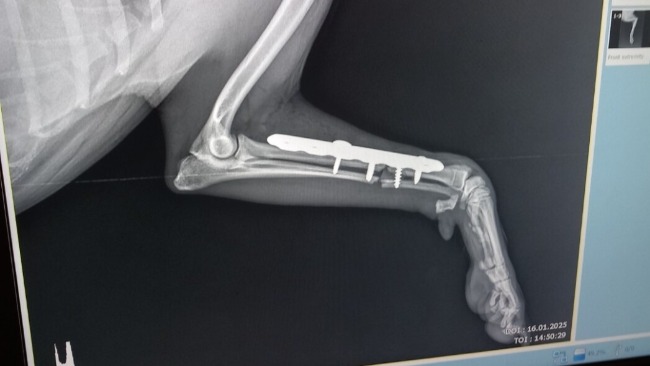

Jesteśmy już po diagnozie i konsultacji chirurgicznej. W badaniu rtg w sedacji cechy obecności płyty kostnej, odłamy kostne niestabilne, wokół wkrętów odczyny zapalne oraz zanik kostny. Co znaczy, że jeżeli nie zoperujemy Koksika czeka go amputacja łapki.

Istnieje jednakże możliwość ponownej operacji osteosyntezy.

Wskazane jest usunięcie obecnych wszczepów, założenie innej płyty , tym razem tytanowej, wykonanie korekcji ukątowania kończyny oraz przeszczep kości gąbczastej w przełom złamania.